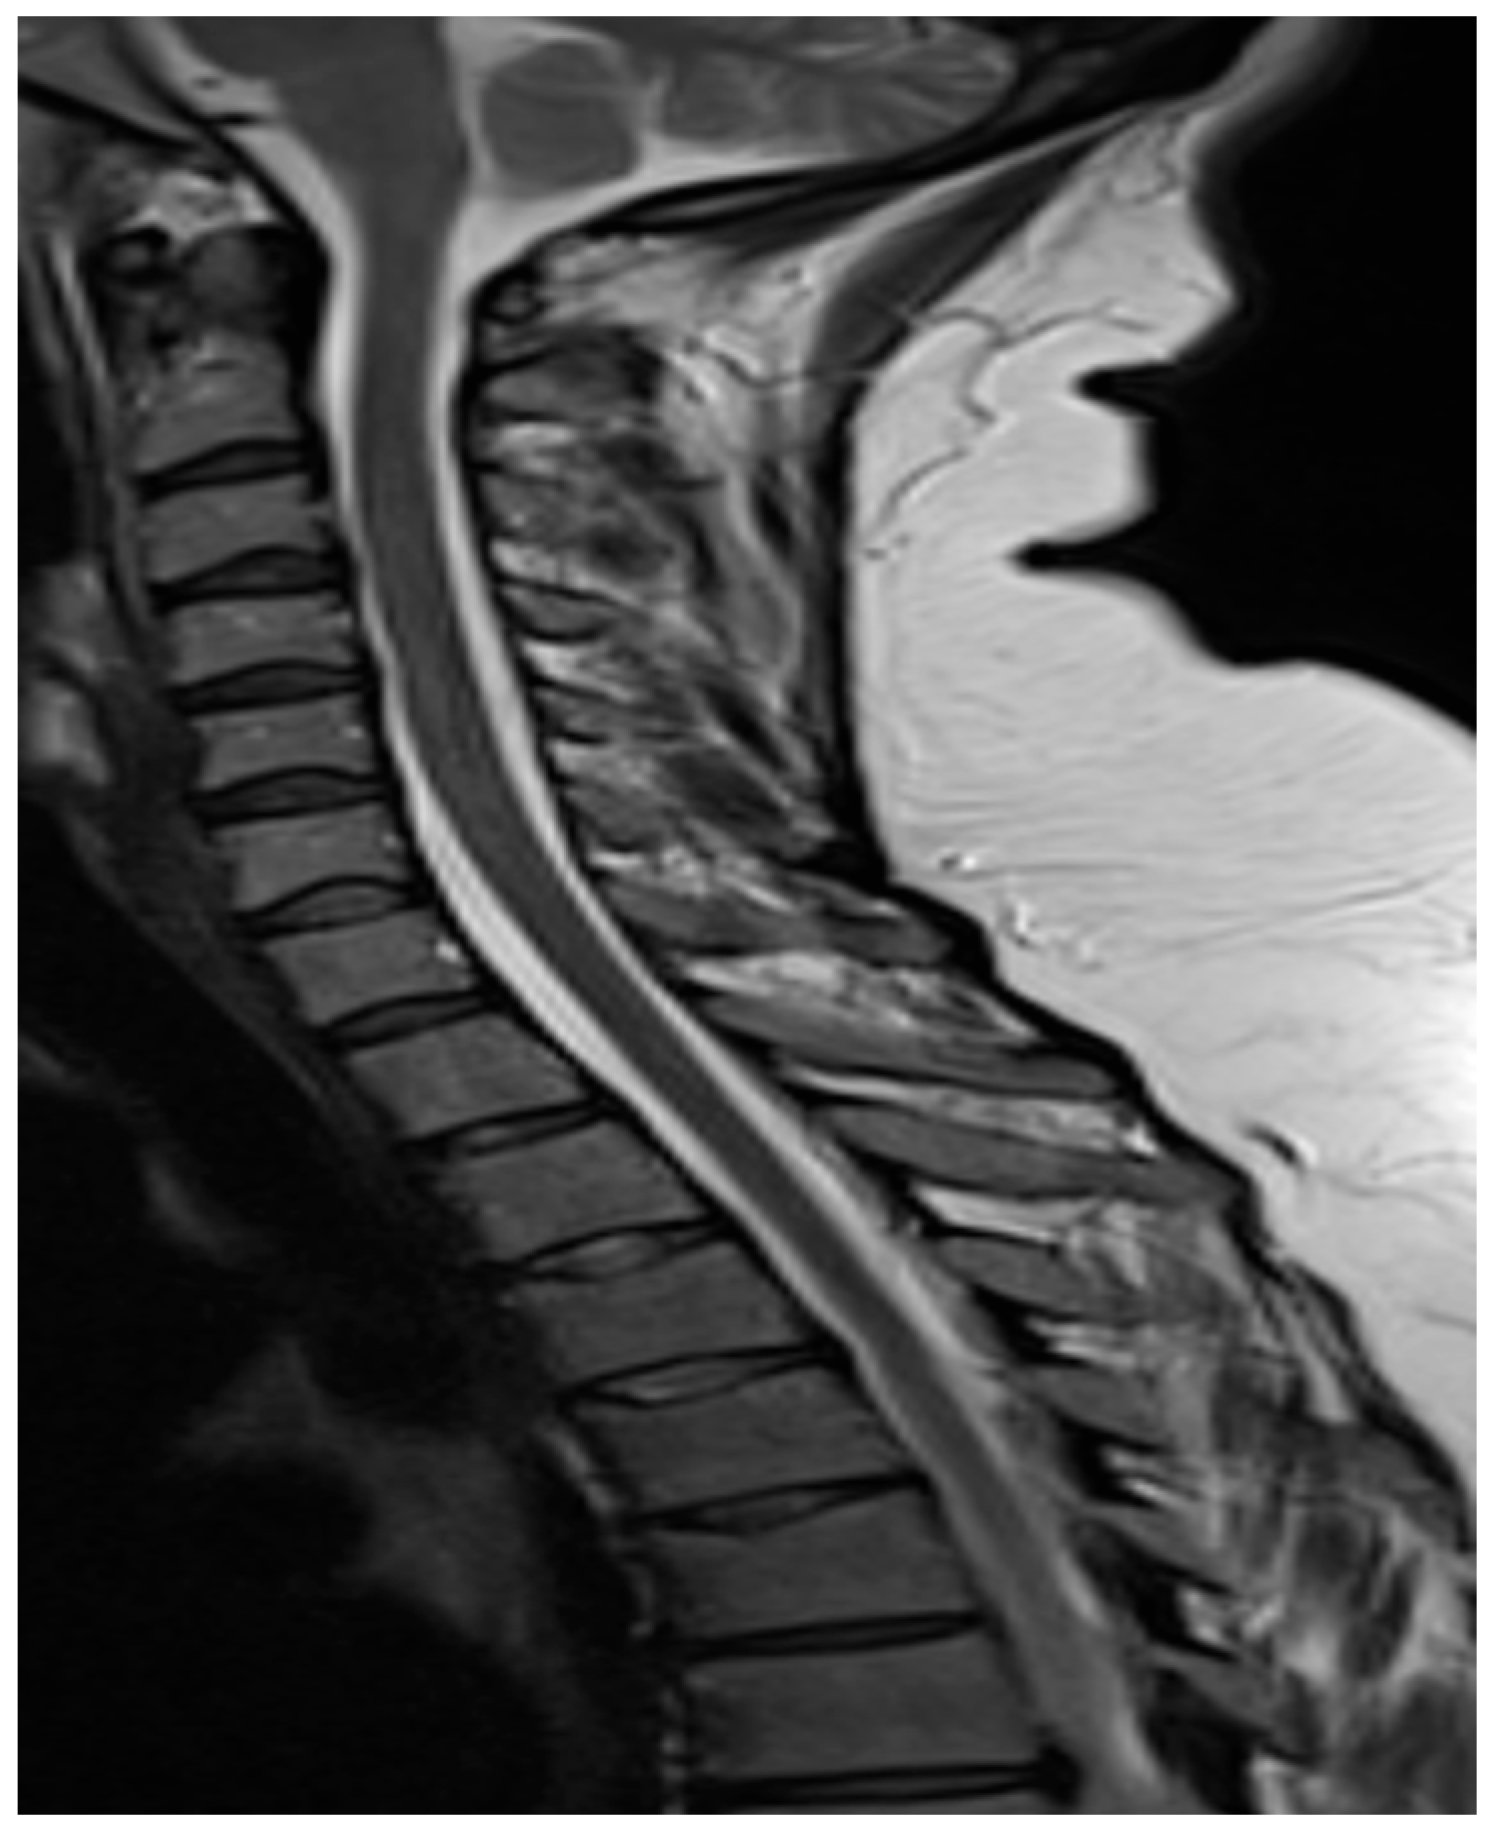

Figure 2. T2-weight MRI Spine sagittal view image shows minimal CSF in the basal cisterns and cerebellar tonsils noted to be lower lying extending beyond the foramen magnum (brain sagging). Persistent extradural CSF is seen within the cervical and thoracic spine, best seen posterior to the C7 vertebral body as circled in red.

She was then assessed by the local neurology team, including neurologists and neurosurgeons, who suspected low-pressure headaches and the possibility of a spontaneous leak. The local neurology multidisciplinary team recommended a repeat MRI head, spine, and orbits at 16 weeks and 3 days of gestation. MRI head, spine, and orbits demonstrated bilateral shallow subdural collections and extradural fluid within the spinal canal, meningeal thickening, and venous engorgement (Figure 1 and Figure 2). The case was discussed in a tertiary-level multidisciplinary team meeting for neuroradiology. A diagnosis of spontaneous intracranial hypotension was established based on the clinical presentation of a thunderclap headache with prominent postural features that worsened on standing, in conjunction with MRI findings of meningeal thickening. This was further supported by lumbar puncture results, which demonstrated xanthochromia and lymphocytic pleocytosis. She was then managed on the lines of treatment for spontaneous intracranial hypotension in pregnancy. She was initially managed with conservative management, including prolonged bed rest, adequate hydration, and avoidance of any strenuous activities such as bending, straining, with the aim of keeping the pain score below 4/10. She was started on prophylactic low molecular weight heparin to prevent the risk of venous thromboembolism in pregnancy. There was still no significant improvement in the headache with regular paracetamol and codeine. Her neurological examination as inpatient had always been unremarkable with no focal neurology.